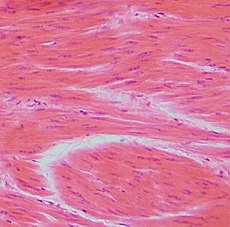

Smooth muscle is composed of individual spindle-shaped cells. Each cell contains a single elongated nucleus located centrally in the wider part of the cell. The size of the cells varies from about 20 μm to 500 μm in the uterine wall during pregnancy. The cells are surrounded by a network of reticular fibers and a basal lamina. These structures serve to evenly distribute the forces and thus enable the contraction to be harmonized.

The plasma membrane is called the sarcolemma, on its inner surface there are plates, the so-called dense bodies. Dense bodies have the function of attachment of thin and intermediate filaments, they are formed by the protein α-actinin, so they are similar to the Z-discs of striated muscle. The sarcolemma creates numerous pinocytic invaginations, individual cells are connected by nexuses. Intermediate filaments mainly contain desmin and vimentin.

The contraction of smooth muscle, like skeletal muscle , is based on the reaction of actin with myosin , but the course of contraction is different. Myofilaments cross each other to form a lattice-like structure, rather than the transverse striations characteristic of skeletal or cardiac muscle. Thin filaments are made of actin and tropomyosin (unlike striated muscles, troponin is missing ), thick filaments are made of myosin. Contraction is initiated by the release of Ca 2+ , which forms a complex with calmodulin. This complex subsequently activates the myosin light chain kinase and its phosphorylation occurs, which enables the formation of the actinomyosin complex. Myosin filaments in smooth muscle differ from myosin filaments in striated muscle in that the ends of the molecule are bare and the heads are in the center of the filament.